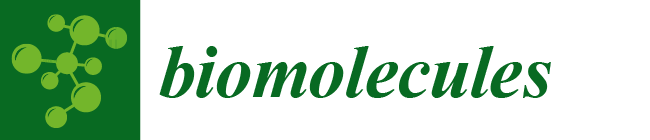

2.2. Experimental Setup

2.3. Tomography

2.7. Verification of the Probe Location and Histology